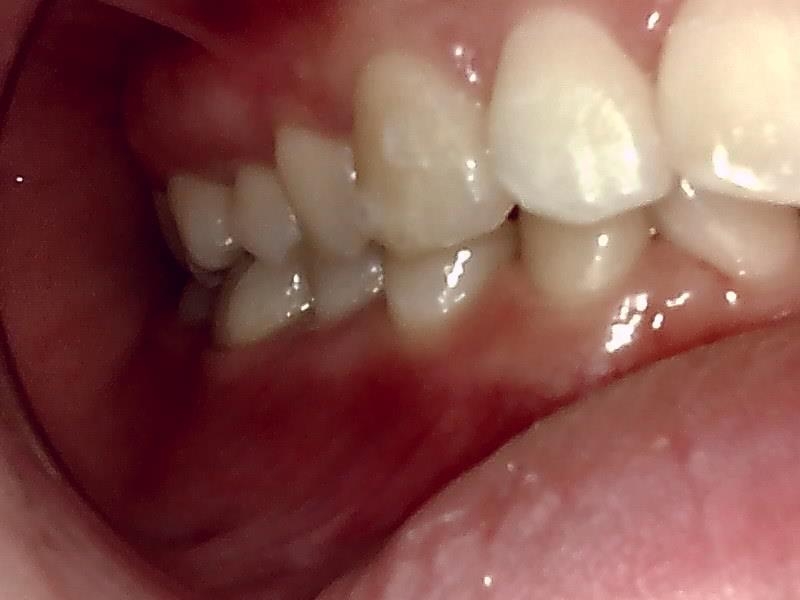

左側

右側